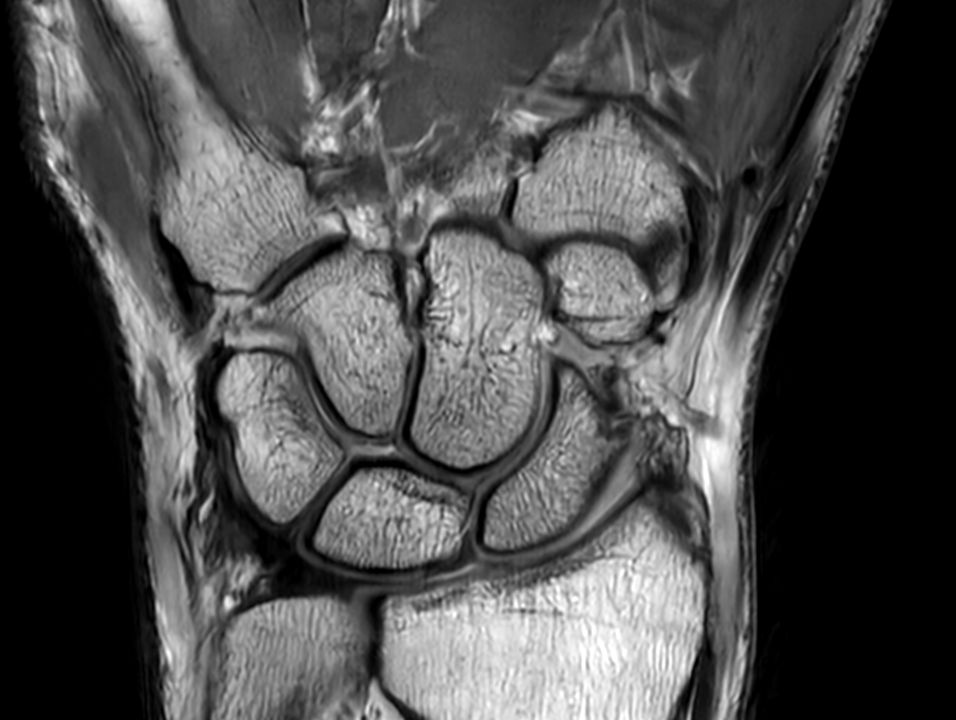

Coronal PDw TSE

Coronal PDw TSESmartSpeed

Coronal PDw TSESmartSpeed High Resolution